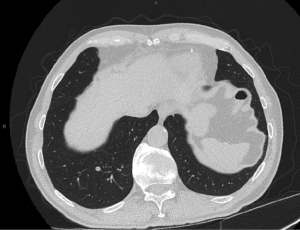

The patient had a same day pre-procedure CT chest performed on arrival at the hospital (Figure 1). This scan was uploaded to PlanPoint planning software (Intuitive Surgical, Inc.). The CT scan was reviewed by the proceduralist, nodule(s) were marked, and pathways were created. The plan was then exported to the RAB system. The patient was intubated by anesthesiology via rapid sequence intubation (RSI) with placement of an endotracheal tube. The patient was paralyzed with non-depolarizing neuromuscular blocking agents and maintained with total intravenous anesthesia (TIVA). The ventilator (Dräger Apollo, Lübeck, Germany) VT was set at 10 cc/kg non-ideal body weight with a target between 500–850 cc, PEEP at 10 cmH2O (12 if morbidly obese), with FiO2 at 100%. The patient’s vital signs, including heart rate, blood pressure, pulse oximetry, electrocardiogram, were monitored non-invasively per institution guidelines for patients undergoing general anesthesia. There was no routine use of arterial blood gas monitoring or transcutaneous CO2 monitoring. Anesthesiology staff treated the patient’s hemodynamic changes during the procedure, as necessary.

The proceduralist performed intraprocedural imaging to localize the PPL, which potentially included r-EBUS (Olympus Corporation of the Americas), 2D fluoroscopy or mCBCT using the Cios-Spin™ Mobile 3D C-Arm (Siemens Healthineers Inc., Erlangen, Germany). After ensuring proper catheter to lesion positioning via confirmation with intraprocedural imaging, the proceduralist performed the biopsy using a multimodality approach that included transbronchial needle aspiration (TBNA, Flexision needle, Intuitive Surgical) and transbronchial lung biopsy (TBBX, Captura mini biopsy forceps without spike, Cook Medical, Winston-Salem, NC, USA) with possible transbronchial lung cryobiopsy (TBLC, 1.1 mm cryoprobe, Erbe USA, Marietta, GA, USA). Figure 4 shows mCBCT with the tool in lesion. Rapid on-site pathology was available via cytotechnician and cytopathologist for immediate evaluation of samples. Apneic oxygenation was stopped after completion of PPL biopsy. If multiple PPLs were evaluated during the procedure, apneic oxygenation was either continuous or with a period of ventilation per the protocol settings in between PPLs. After the final target PPL, the ventilator was set according to the anesthesia provider’s preference.